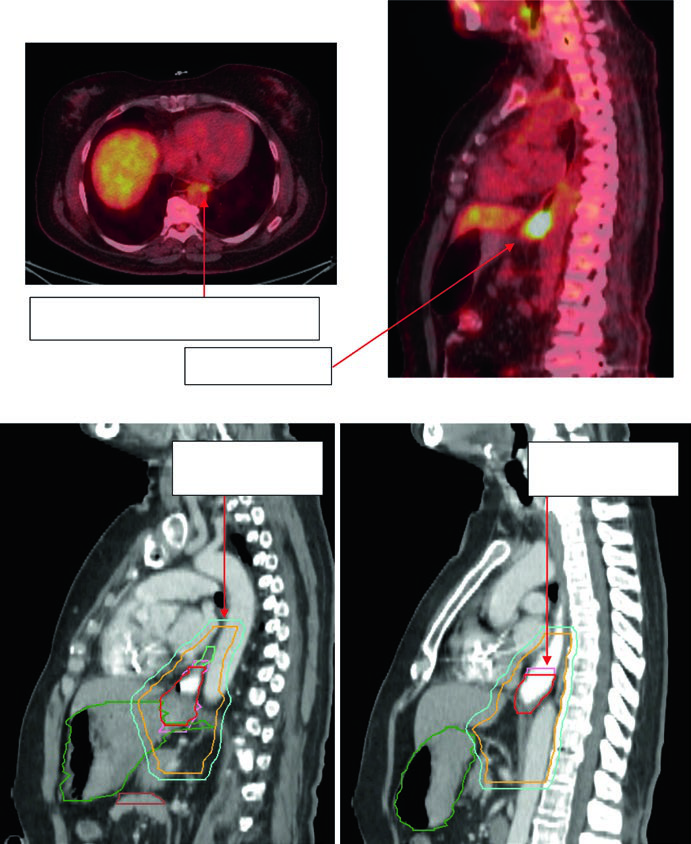

Case 2: Lower Thoracic Adenocarcinoma — 81-Year-Old, uT3N1

An 81-year-old patient with lower thoracic esophageal adenocarcinoma uT3N1. PET showed primary uptake and level 4R paratracheal lymph node. Endoscopy revealed a partially obstructing circumferential adenocarcinoma 31–35 cm from the incisors. EUS confirmed T3 primary disease with suspicious level 4R node. Contours applied a 0.5 cm GTV-to-CTV margin for the 4R node and 3–4 cm inferior coverage. Volumes: brachial plexus (purple), stomach (dark green), esophageal GTV (red), ITV (pink), nodal GTV (light green), CTV (orange), PTV 50.4 Gy (dark blue).

Case 3: GEJ Adenocarcinoma — 75-Year-Old, uT3N0

A 75-year-old patient with GEJ adenocarcinoma uT3N0. Contours demonstrate CTV extension into the proximal stomach with coverage to the celiac axis. Delineated volumes: stomach (dark green), large bowel (brown), esophageal GTV (red), CTV (orange), PTV 50.4 Gy (cyan). Celiac axis coverage is mandatory for distal and GEJ tumors.